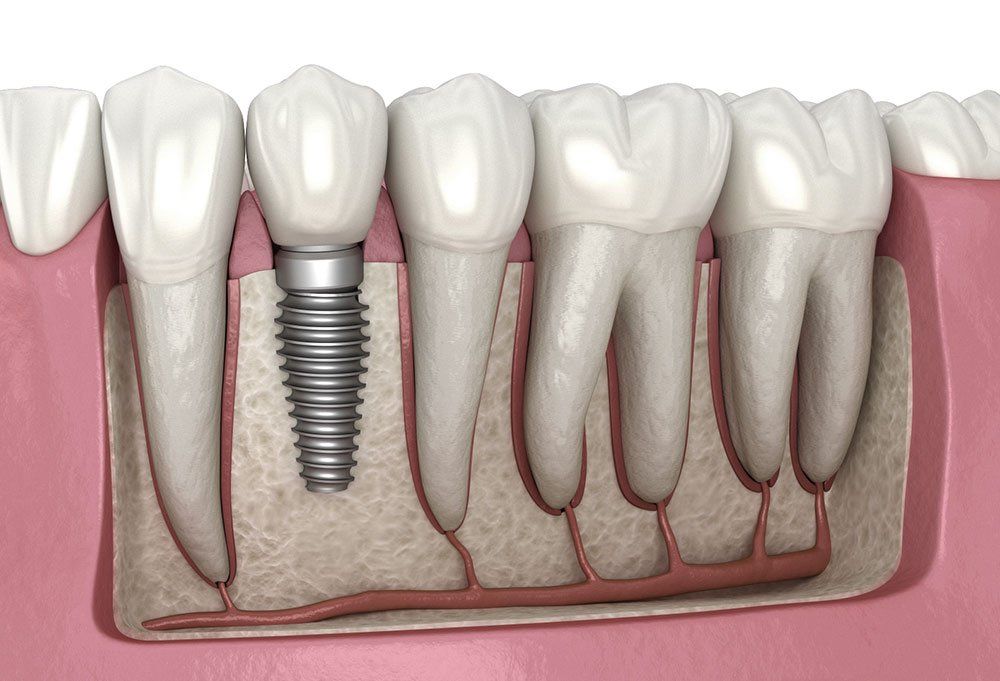

Myönnän auliisti, että lähtökohta tälle narinalle on niin sanottu ”oma lehmä ojassa” -tilanne. Haljenneen takahampaan poisto kunnallisessa hammashoidossa on muutaman kympin maksava kivulias toimenpide. Mutta verrattuna implantin laittoon tuska sekä fyysisesti että henkisesti on vähäinen. Implantin hinta on tällä hetkellä 3000 euroa ja toimenpiteet kestävät viikkoja. Minulla olisi tarvetta kahdelle. Kuusi donaa on helvetin iso läjä rahaa. Onneksi kyseessä ovat äärimmäiset kulmahampaat. Ilman niitä tulee toimeen. Minun ei tarvitse ”yrittää mukeltaa aamupalaani” kuten Ludde 14.